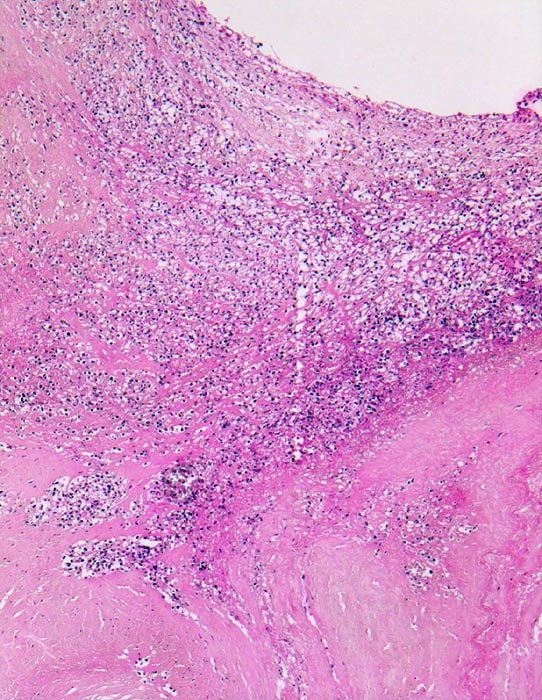

Histologisch findet sich bei ulzeropolypöser Endokarditis ein Fibrin-Thrombozytenthrombus, welcher von Bakterien durchsetzt ist (=Vegetation). Die Vegetation sitzt auf einem Klappendefekt an dessen Basis Granulationsgewebe einzusprossen beginnt, welches den Thrombus organisiert. Klappendefekte, Gefässeinsprossungen, verdickte Sehnenfäden (> 2848) oder Kommissurenverwachsungen (> 8389) der Taschenklappen weisen morphologisch auf eine abgeheilte Endokarditis hin.

• Längsschnitt durch Aorta, Aortenklappe und linkes Ventrikelmyokard.

• Abszedierende Entzündung der aortalen Adventitia ausgehend von septikopyämischen Streuherden.

• Ulzerierte Aortenklappe(ulcerosa).

• Dem ulzerierten Klappengerüst aufgelagerte polypöse Vegetation aus Fibrin und Granulozyten durchsetzt von blauen Kokkenbakterienkolonien (polyposa).

• Ausgedehnte frische Koagulationsnekrose (unsichtbare Zellkerne, Infiltrate neutrophiler Granulozyten) des linken Ventrikelmyokards unterhalb der Klappe.

• Mehrere septikopyämische Streuherde (blaue Bakterienhaufen in intramyokardialen Blutgefässen umgeben von Mikroabszessen).